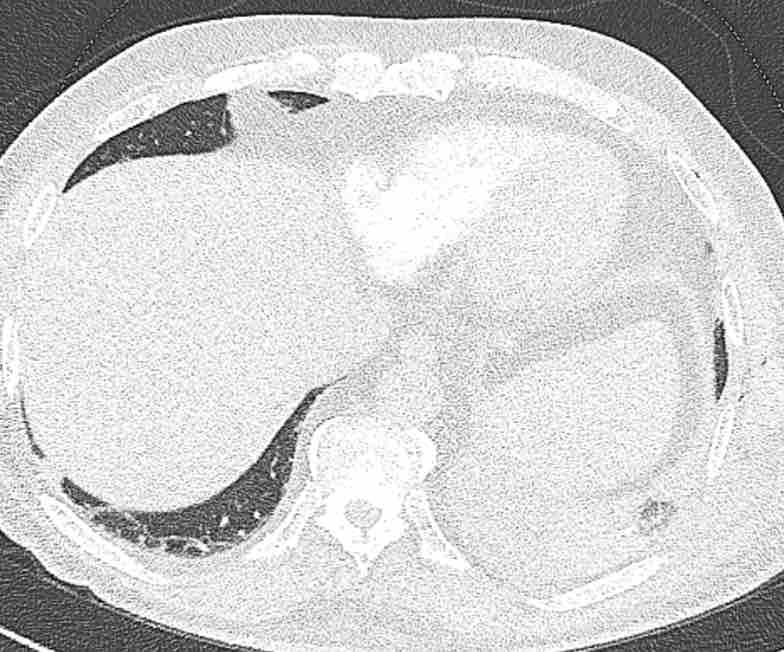

Hình ảnh

Cuộn qua các hình ảnh.

Theo dõi các phế quản của thùy dưới phổi trái cho thấy nhánh phân thùy đầu tiên của thùy dưới phổi trái còn thông; đó là phế quản phân thùy đỉnh.

Các ghim phẫu thuật nằm tại vị trí của các phân thùy đáy sau và đáy bên (LB9/10), vốn thường được cắt bỏ cùng nhau.

Do đó, phân thùy phổi có hình ảnh kính mờ và đông đặc phải là phân thùy đáy trước của thùy dưới phổi trái (LB8).

Động mạch phổi đến phân thùy này cũng không ngấm thuốc cản quang, và bản đồ tưới máu iốt nhấn mạnh thêm tình trạng nhồi máu.

Bệnh nhân đã được phẫu thuật lại và tiến hành cắt bỏ phân thùy bị nhồi máu, với xác nhận qua giải phẫu bệnh.

Trên bản đồ tưới máu iốt, có sự tưới máu ở thùy trên phổi trái và phân thùy đỉnh của thùy dưới phổi trái, nhưng không có sự tưới máu ở phân thùy đáy trước của thùy dưới phổi trái.